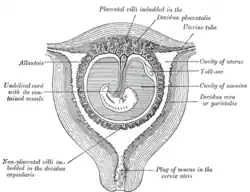

Sectional plan of the gravid uterus in the third and fourth month. | |